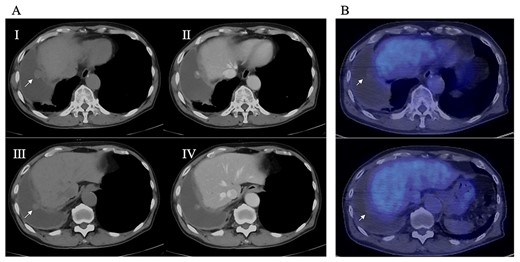

An 81-year-old man who underwent surgical resection for lung cancer 2 years previously was referred for the examination of a right diaphragmatic mass that was pointed out during follow-up. Computed tomography (CT) revealed pleural effusion and two contrast-enhanced nodules (17 × 10 and 10 × 10 mm) in the right diaphragm (Fig. 1A); however, he had no symptoms. Positron emission tomography (PET)/CT was performed, but no FDG accumulation was found (Fig. 1B). Although hemangioma was suspected based on the preoperative imaging, we were unable to exclude the recurrence of lung cancer. Therefore, the patient was admitted for the examination of the right diaphragmatic nodules by VATS. A 4-cm thoracotomy wound was created at the 8th intercostal mid-axillary line, and a 5.5-mm port was created at the 6th intercostal anterior axillary line. Observation of the thoracic cavity revealed reddish brown pleural effusion and two large and small pedunculated tumors on the diaphragm (Fig. 2). The smaller nodule spontaneously fell off during the process of cleaning the thoracic cavity and was submitted for a rapid intraoperative diagnosis. As hemangiomas were diagnosed during the operation, the roots of the smaller nodule and the larger nodule that fell off were treated using an ultrasonic coagulation and incision device while partially leaving the abdominal layer of the diaphragm. Partial excision was performed (Fig. 3). The nodules were 1.7 × 1.7 and 1.5 × 1.5 cm with a brown surface (Fig. 4). Histopathologically, the nodules were mostly blood clots, and a collection of thin-walled blood vessels with red blood cells was observed (Fig. 5A). An immunohistochemical analysis revealed that the vascular endothelial cells were positive for CD31 and CD34 (Fig. 5B). Thus, the nodules were diagnosed as diaphragmatic hemangioma. No hemangiomatous lesions were noted in the normal connective tissue in the additional resected tissue specimens (Fig. 6). The postoperative course was normal, and the patient is being followed up in an outpatient setting. It has been 16 months since the operation, but no recurrence has been observed at this time.

(A) Preoperative CT; right pleural effusion was present, and a 17 × 10 mm nodule (I) and a 10 × 10 mm nodule (III) were found on the right diaphragm; contrast medium staining from the center (II, IV), and (B) preoperative PET-CT; no accumulation of FDG was observed in the diaphragmatic nodules.